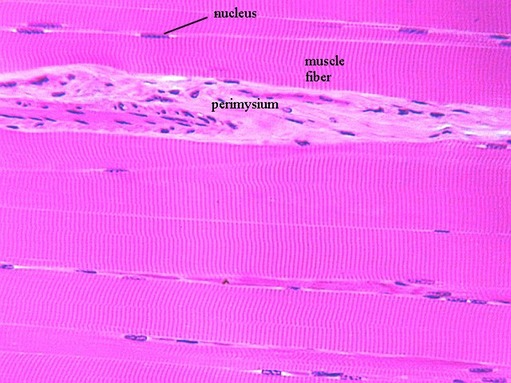

Above is a photograph of skeletal muscle cut in longitudinal section. The thin blue nuclei are found at the periphery of each cell or fiber (which is multinucleated). You can also see the striations. In the middle of the section is a connective tissue division, called "perimysium”.